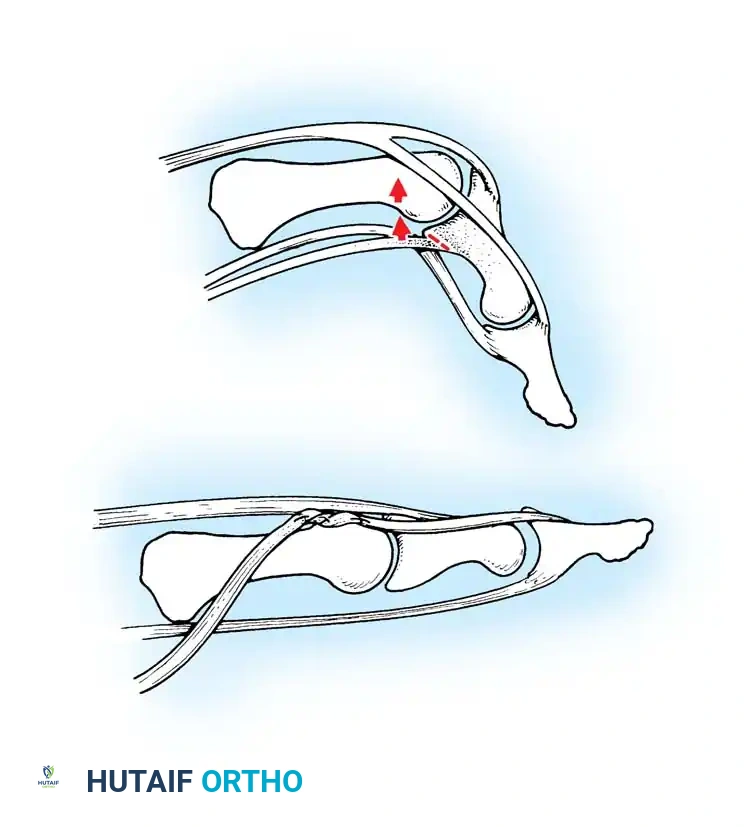

Anatomical diagram illustrating the mismatch between the hypertrophied intratendinous nodule and the stenotic A1 pulley.

A critical distinction must be made between congenital trigger fingers and trigger thumbs. Trigger fingers are less likely to present with a fixed flexion deformity. More importantly, they frequently do not respond to a simple A1 pulley release.

When surgical intervention for a trigger finger is undertaken, the surgeon must be prepared for a comprehensive exploration of the flexor mechanism. The pathology often extends beyond the A1 pulley, involving abnormal decussations of the flexor digitorum superficialis (FDS) or stenosis at the A3 pulley.

Intraoperative visualization of the flexor tendon sheath, highlighting the critical relationship between the A1 and A2 pulleys.